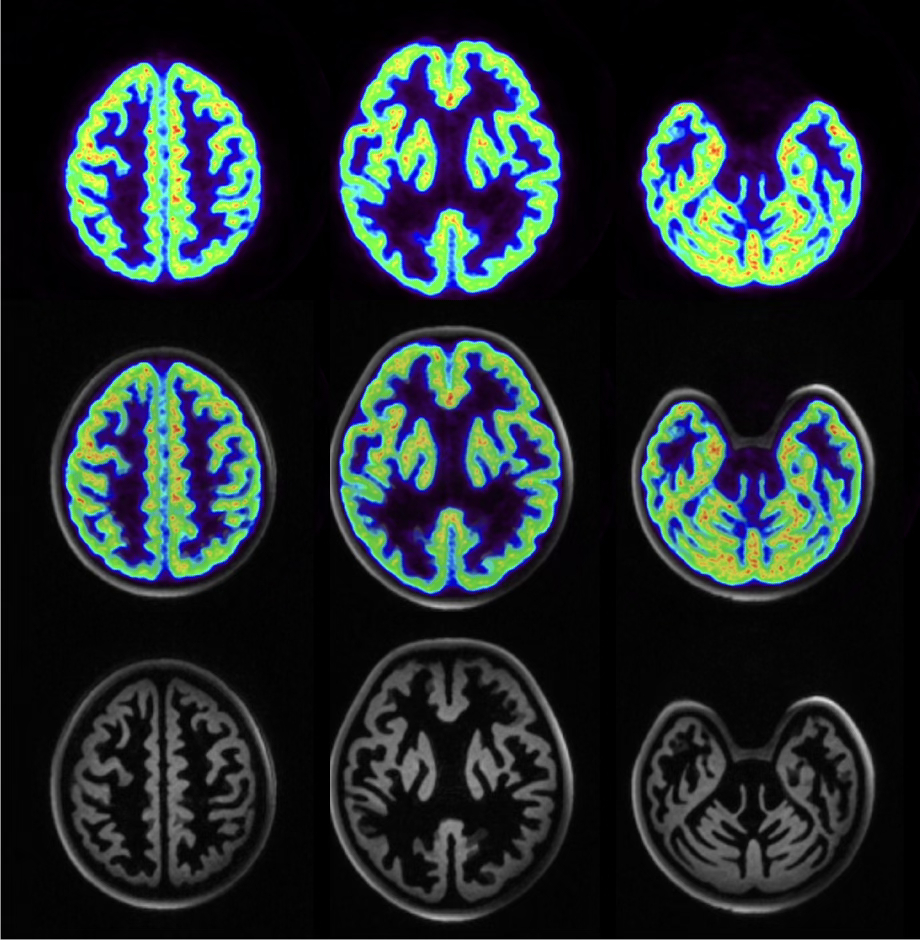

Die Forschungs- und Entwicklungsarbeiten unserer Institutsbereiche der Physik der Medizinischen Bildgebung (INM-4) des Instituts für Neurowissenschaften konzentrieren sich auf die Entwicklung, experimentelle Validierung und klinische Prüfung neuer Bildgebungsmethoden des Gehirns.

Jülicher Bildgebungstechnik ermöglicht präzise Einblicke in Struktur und Funktion des menschlichen Gehirn